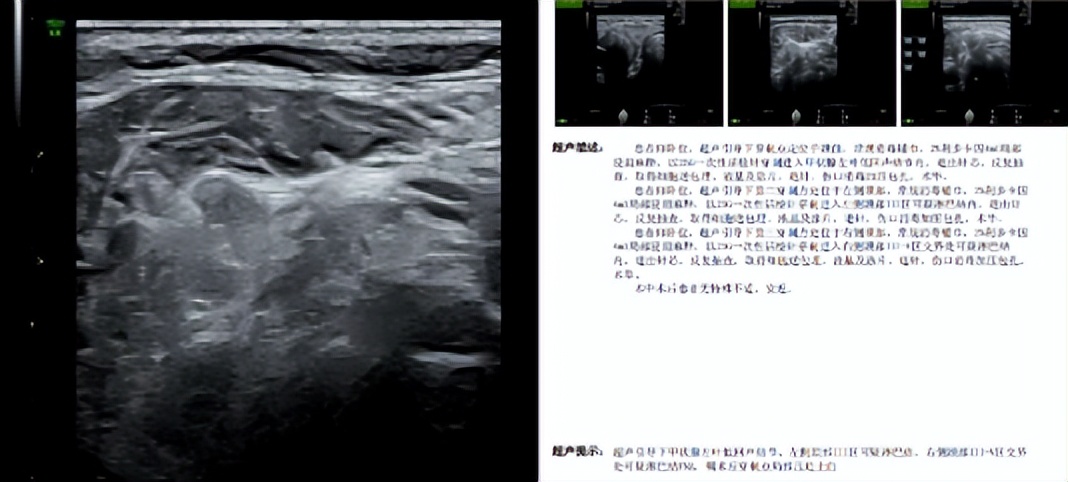

在此基础上,该院陆港院区超声医学科再度攻克技术难关,为一名外院提示甲状腺4类结节的患者开展超声引导下双侧颈部淋巴结及甲状腺可疑恶性结节细针穿刺术。该患者经魏炜副主任超声会诊,被明确为甲状腺左叶5类结节及双侧颈部广泛可疑淋巴结,符合穿刺指征。在详细告知患者病情、穿刺意义和风险并取得同意后,医疗团队在高分辨率超声实时动态引导下,精准避开甲状腺周围重要血管、神经及气管,分别对甲状腺左叶5类结节、左侧颈部III区可疑淋巴结、右侧颈部III-V区交界处可疑淋巴结进行穿刺,成功抽取满意的细胞学样本。操作过程顺利,患者无明显不适及并发症,术后恢复良好。

本次穿刺获取的高质量细胞学样本满足了病理诊断需求。甲状腺细胞涂片及蜡块切片中可见“细胞异型及核沟”,提示甲状腺乳头状癌,BRAF基因V600E未检出到突变;左侧颈部III区及右侧颈部III-V区交界处淋巴结穿刺样本提示甲状腺乳头状癌转移,且淋巴结穿刺液测得甲状腺球蛋白(Tg)>500,呈高表达,为诊断提供了强有力的佐证,患者最终被确诊为甲状腺乳头状癌并双侧颈部淋巴结转移。